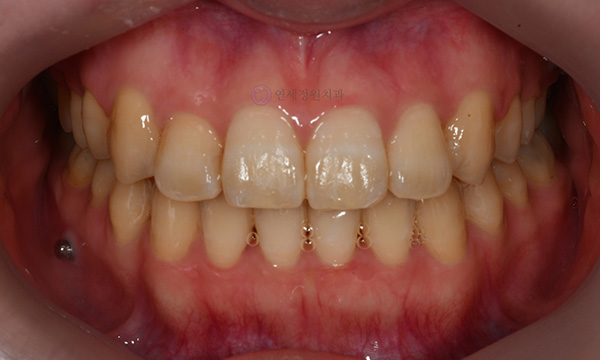

위 환자분은 치아 중심선이 맞지 않는다는 주소로 치과에 내원하셨습니다. 미소시 사진을 보면 위 치아도 오른쪽(사진 상 왼쪽)으로 틀어져 있고, 아래 치아도 왼쪽(사진 상 오른쪽)으로 틀어져 있었습니다. 그리고 양쪽 입꼬리 근육의 활성도도 차이가 있어서, 웃었을 때 왼쪽 입꼬리가 오른쪽보다 덜 올라가서 비대칭이 더 강조되어 보였습니다.

2020.7

치아 중심선의 차이를 개선하고, 얼굴의 중심과 치열의 중심을 맞춰주기 위하여 오른쪽 아래 작은 어금니를 하나만 발치하여 그 공간으로 아래 치열을 오른쪽으로 돌려주고, 위 치열은 전체적으로 왼쪽으로 치열을 이동시켜서 중심선을 맞추어 주었습니다.

2022.6

위 아래 치아의 중심선이 일치하고 좌우 어금니의 교합도 잘 맞춰졌습니다. 좌우 입꼬리 올림근 활성도의 차이는 남아있음에도 얼굴의 중심과 위 아래 치아의 중심이 일치하여 미소시에도 교정 전보다 훨씬 자연스러운 미소를 짓게 되었습니다.